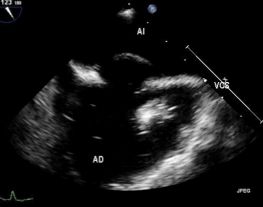

Foramen ovale permeable. A propósito de un caso.

Imágenes